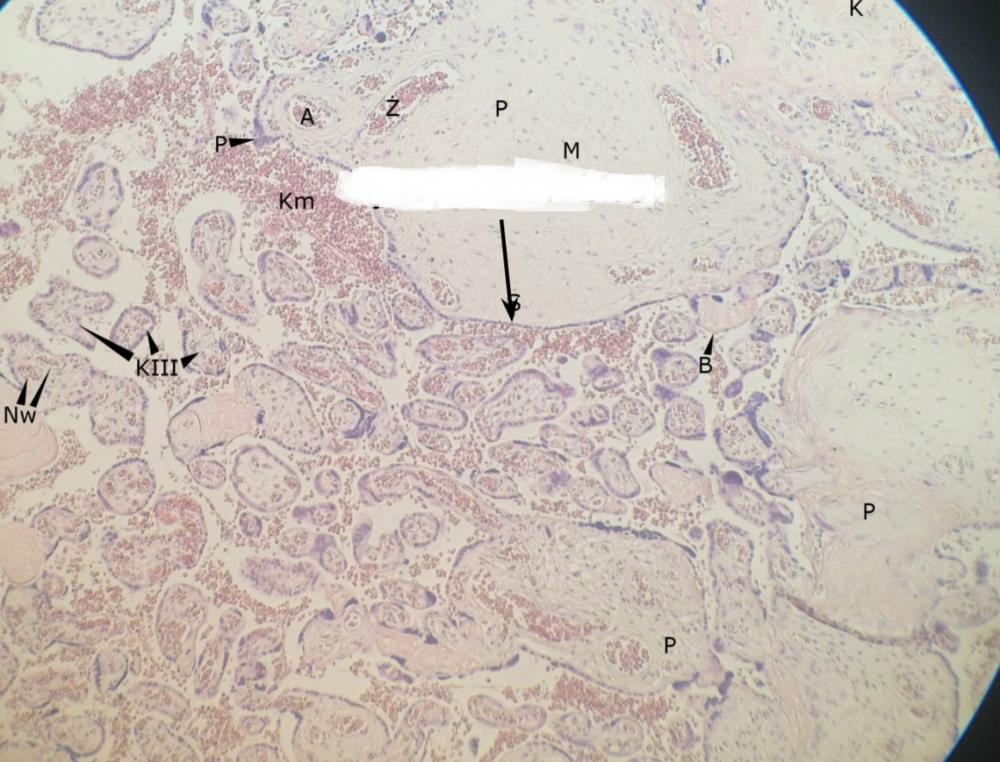

pnie kosmówkowe (łożysko, płyta kosmówkowa)

kosmki końcowe (łożysko, płyta kosmówkowa)

syncytiotrofoblast (łożysko, płyta kosmówkowa)

węzły syncytiotrofoblastu - jądra komórkowe (łożysko, płyta kosmówkowa)

płytki nabłonkowo-naczyniowe - cytoplazma bez jąder (łożysko, płyta kosmówkowa)

erytrocyty matki (łożysko, płyta kosmówkowa)

erytrocyty płodu (łożysko, płyta kosmówkowa)

przegroda łożyskowa (łożysko, płyta kosmówkowa)

komórki doczesnowe (łożysko, płyta kosmówkowa)

komórki kotwiczące (łożysko, płyta kosmówkowa)

naczynia włosowate (łożysko, płyta kosmówkowa)